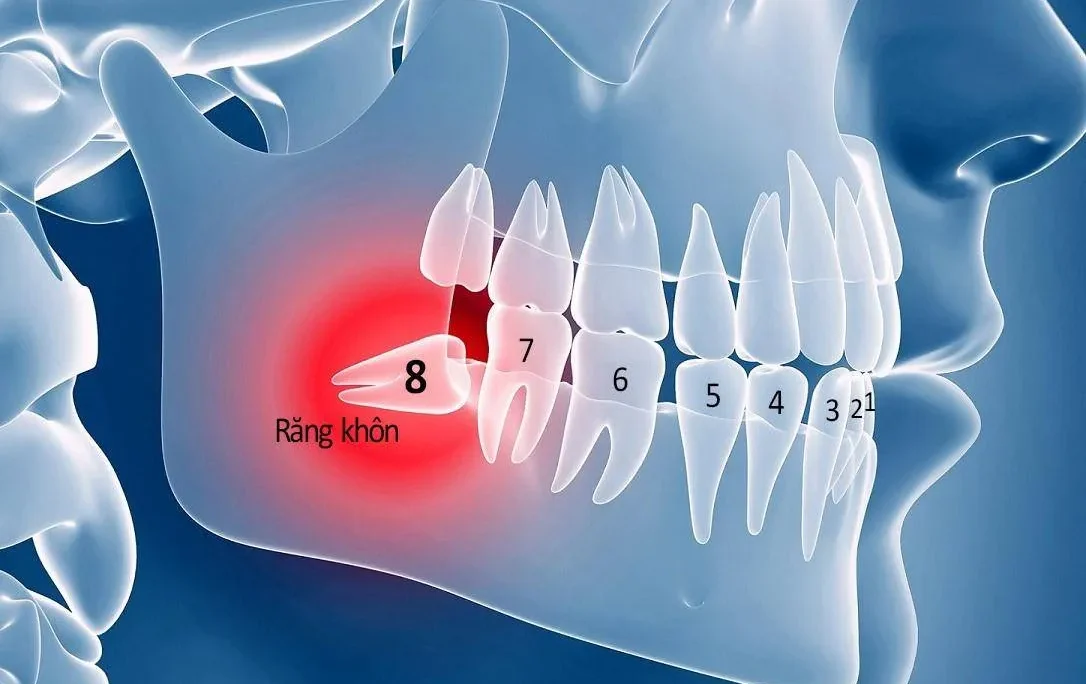

Nguyên nhân chính gây ra móm là do cấu trúc xương hàm và trị mọc của những chiếc răng. Các loại móm có thể chia làm 2 loại chính như sau:

Móm do răng

Móm do răng là tình trạng khá phổ biến, là tình trạng sai lệch khớp cắn, hay còn được gọi là căn ngược hoặc cắn chéo. Biểu hiện của tình trạng này là: khi cắn lại, răng cửa của hàm dưới nằm ngoài răng cửa hàm trên. Trong khi xương hàm của người bệnh vẫn phát triển bình thường với kích thước tiêu chuẩn được đưa ra.

Móm do hàm

Biểu hiện của móm do hàm đó là xương hàm phát triển quá mức bình thường, nhô ra bên ngoài; hoặc xương hàm trên chậm phát triển nên có cảm giác đang thụt vào trong; hoặc do cả hai nguyên nhân này. Khi đó xương hàm dưới sẽ bao phủ toàn bộ răng hàm trên, dù những chiếc răng mọc đúng vị trí.